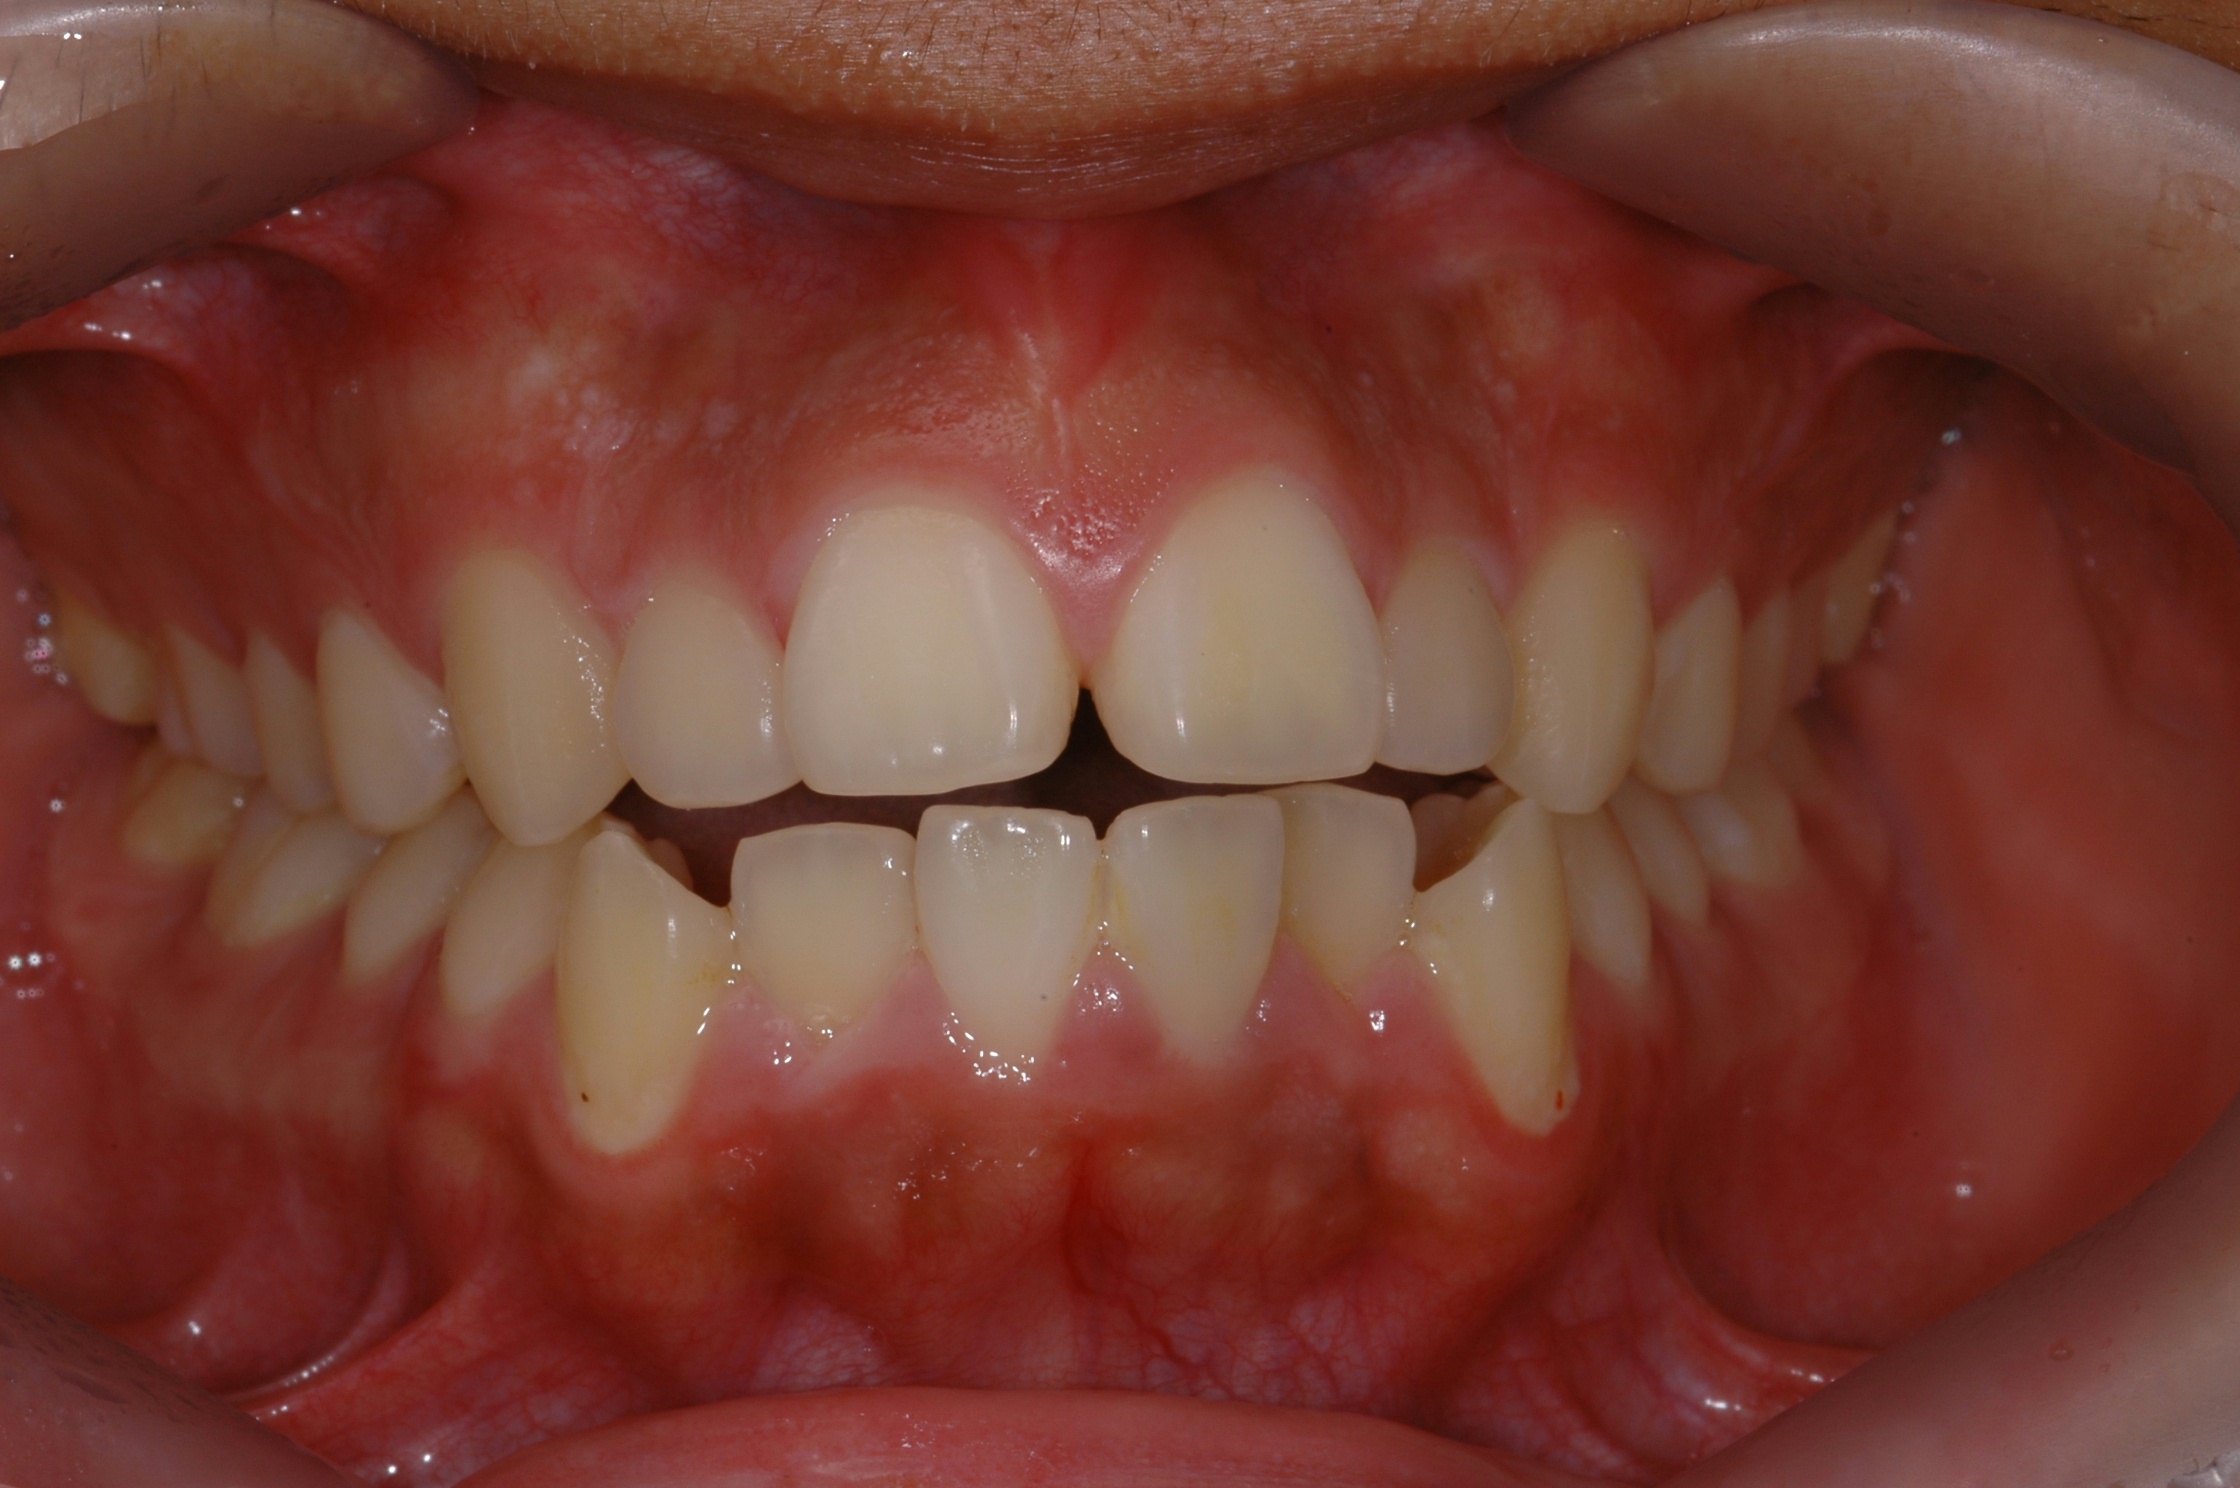

치료 전 사진입니다.